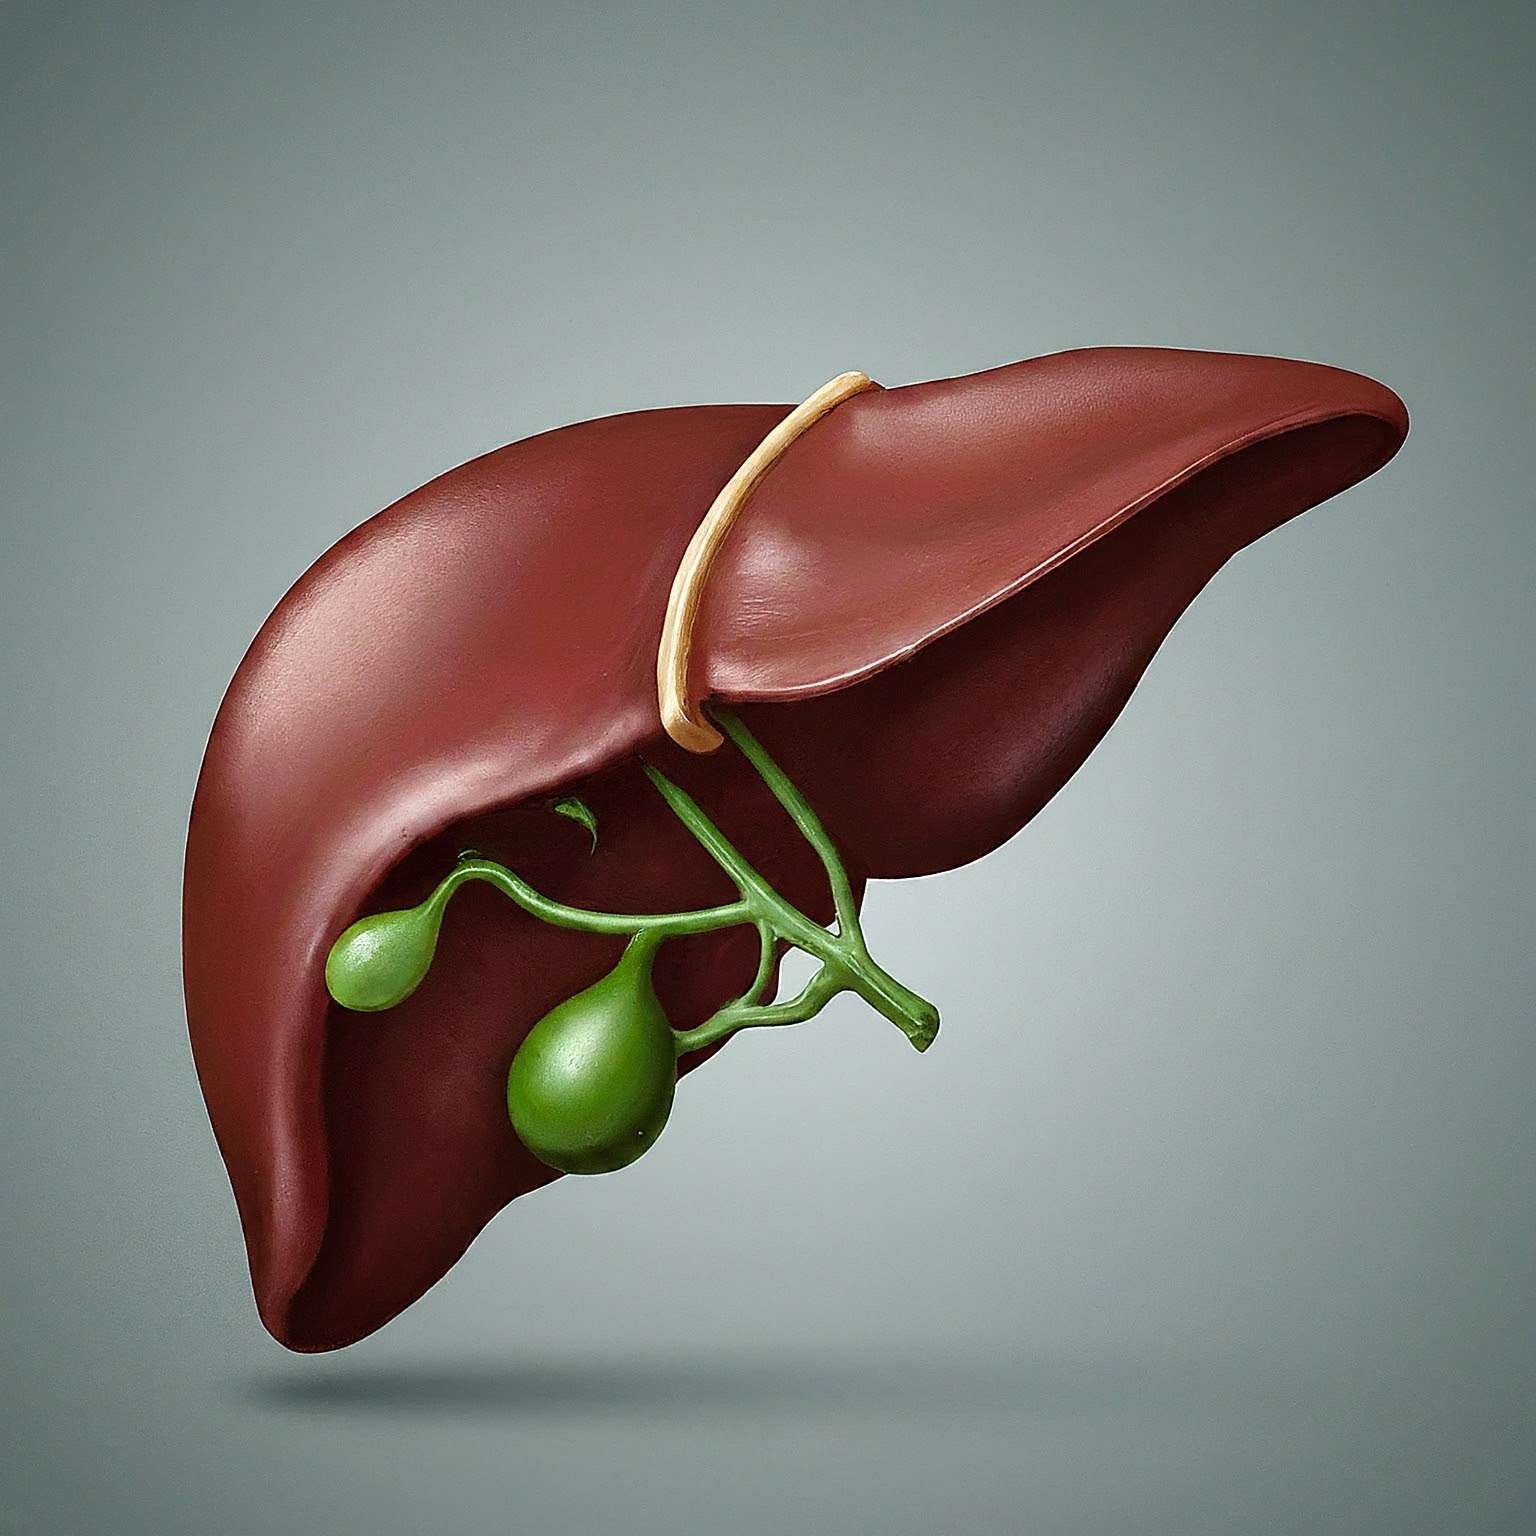

“The liver, often referred to as the body’s detox powerhouse, plays a crucial role in maintaining overall health. While many are aware of the dangers of alcohol consumption for liver health, other less obvious culprits lurk in our diets. High-fructose corn syrup (HFCS), trans fats, excessive sugar, and sodium-laden foods pose significant threats to our liver’s well-being. HFCS, prevalent in processed foods, contributes to fatty liver disease, while trans fats found in fried foods increase inflammation. Excessive sugar intake overloads the liver, leading to fat accumulation, and sodium-rich foods can exacerbate liver dysfunction. To safeguard liver health, it’s vital to prioritize whole foods, limit alcohol consumption, and engage in regular exercise. By making conscious dietary choices and adopting a healthier lifestyle, we can protect our liver from harm and optimize our overall health and vitality.”